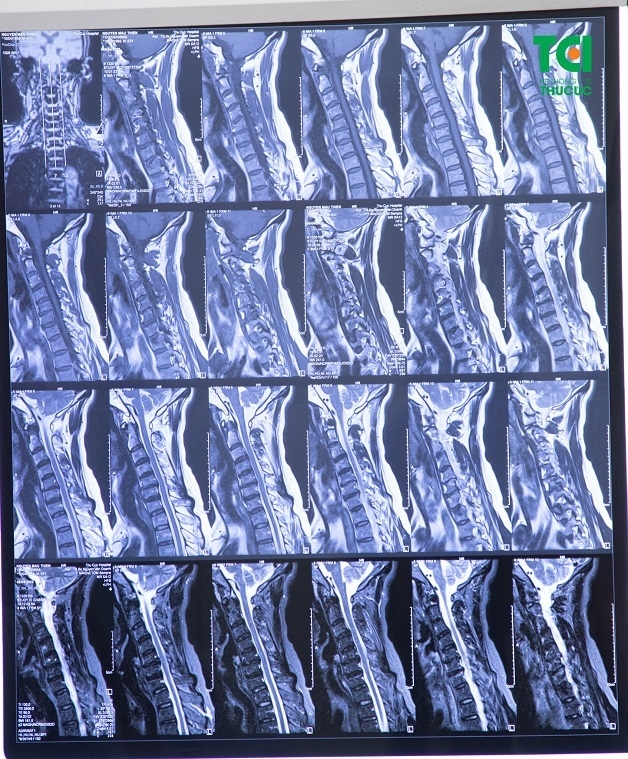

Một số kỹ thuật cận lâm sàng thường được chỉ định trong trường hợp người bệnh đau cột sống cổ là: xét nghiệm, chụp x quang cột sống cổ, chụp cộng hưởng từ vùng cột sống cổ, chụp cắt lớp vi tính cột sống cổ,…

Hình ảnh thoái hóa cột sống cổ trên phim chụp cộng hưởng từ cột sống cổ tại Thu Cúc TCI.